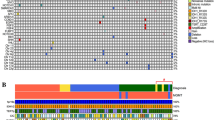

Molecular genetic analysis was performed by extracting DNA from FFPE material using the Maxwell system (Promega) according to the manufacturer’s protocol and subsequent application of the Illumina Focus Panel (Illumina) on an Illumina MiniSeq device (Illumina) according to the manufacturer’s protocols enabling us to analyze 41 genes in parallel, including IDH1 and IDH2 hot spot regions (the complete gene list can be found in Table 1). Hot spot loci of TERT promoter were analyzed by Sanger sequencing [4, 7]. DNA-methylation profiling was performed using Illumina EPIC bead chips that were scanned on an Illumina NextSeq 550DX device. Data analysis was performed using the Molecular Neuropathology Pipeline of the German Cancer Research Center (DKFZ) [1].

Integrated work-up of the first tumor manifestation showed an IDH1 R132H mutation (Fig. 3a) with IDH2 wildtype (Fig. 3b) and TERT C250T promoter mutation (Fig. 3c). DNA Methylation profiling showed methylated MGMT promoter (Fig. 3d), 1p and 19q losses in copy number profiling (Fig. 3e) and allocated the tumor to the methylation class of oligodendroglioma IDH mutated 1p/19q co-deleted (Fig. 3f).

Molecular genetic findings. The first tumor manifestation showed an IDH1 R132H mutation (a) with IDH2 wildtype (b) and TERT C250T promoter mutation (c). DNA Methylation profiling showed methylated MGMT promoter (d), 1p and 19q losses in CNP (e) and allocated the tumor to the methylation class of oligodendroglioma IDH mutated 1p/19q co-deleted (f). The recurrence showed IDH1 R132H mutation (g) with IDH2 wildtype (h) and TERT C250T promoter mutation (i). DNA-methylation profiling showed methylated MGMT promoter (j), 1p and 19q losses in CNP (k) and allocated the tumor to the methylation class of oligodendroglioma IDH mutated 1p/19q co-deleted (l). The second tumor showed IDH1 wildtype (m), IDH2 wildtype (n) and TERT C228T promoter mutation (o). DNA Methylation profiling showed unmethylated MGMT promoter (p), no 1p and 19q loss in CNP (q) and allocated the tumor to the methylation class of glioblastoma IDH wildtype, subclass RTK I (r). *: indication of IDH1 and TERT mutations and 1p/19q losses

Analysis of the recurrence revealed an analogous molecular profile: The tumor showed an IDH1 R132H mutation (Fig. 3g) with IDH2 wildtype (Fig. 3h) and TERT C250T promoter mutation (Fig. 3i). DNA Methylation profiling showed methylated MGMT promoter (Fig. 3j), 1p and 19q losses in copy number profiling (Fig. 3k) and allocated the tumor to the methylation class of oligodendroglioma IDH mutated 1p/19q co-deleted (Fig. 3l).

Interestingly, profiling of the left-sided tumor manifestation revealed a fundamentally different profile: This tumor showed IDH1 (Fig. 3m) and IDH2 wildtype (Fig. 3n) and TERT C228T promoter mutation (Fig. 3o).

DNA Methylation profiling showed unmethylated MGMT promoter (Fig. 3p); there was no 1p and 19q loss in copy number profiling (Fig. 3q) and allocated the tumor to the methylation class of glioblastoma IDH wildtype, subclass RTK I (Fig. 3r).